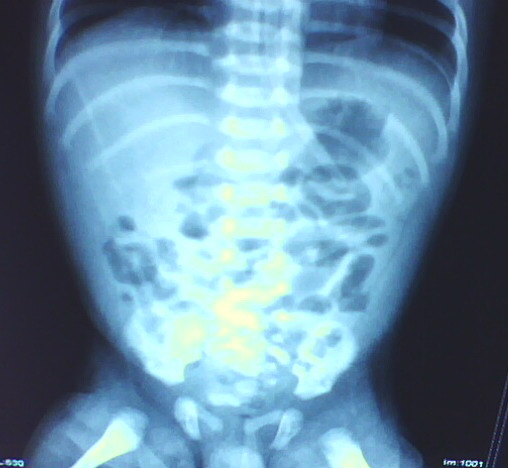

以下是引用拾荒者在2009-10-14 20:41:00的发言:[br]要查的话也应该做钡灌肠,看有否巨结肠及乙状结肠冗长症等;做上消化道钡餐想看什么?5天的小儿肠腔胀气是正常的。